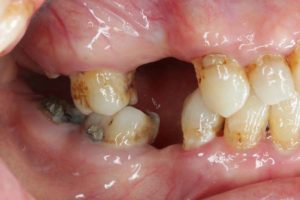

- 術前

- 術後

- インプラント手術直後のレントゲン

長い間お疲れさまでした。この方は、前歯に審美的なインプラントを入れるため、抜歯後4ヶ月待ち、仮歯で歯肉が成熟するのを数が月待っていたりした為に、完成まで時間がかかってしまいました。

虫歯治療などは短期間で終えることができるのですが、歯ぐきをいじり出すとどうしても治癒期間が必要となり長くなってしまいます。それもこれも奇麗な仕上がりのために欠くことのできないものです。何卒ご容赦を!